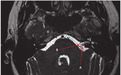

图为高分辨率 T2 加权轴位 MRI,提示左侧内听道(IAM)有一条明显的血管(箭头 A)延伸至 IAM,导致第八脑神经(箭头 B)受到压迫,诊断为:前庭阵发症(vestibular paroxysmia,VP)。

本例患者服用卡马西平后症状消失。VP 是一种自发性、短暂性和反复发作的眩晕,发作通常不是由头部运动触发的, 发作时长通常小于 1 分钟,发作频率高。典型 MRI 表现就是第八脑神经的神经血管压迫。